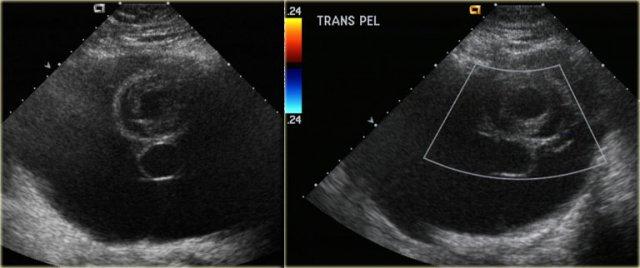

Các hình ảnh siêu âm cho thấy nhiều tổn thương buồng trứng phải đơn giản và một tổn thương phức tạp (mũi tên đỏ).

Tổn thương sau biểu hiện hồi âm mức thấp lan tỏa và không có tín hiệu dòng chảy trên Doppler.

Lưu ý có xuyên âm tốt (mũi tên xanh).

Các đặc điểm này gợi ý sự hiện diện của nang xuất huyết.

Các hình ảnh siêu âm cho thấy buồng trứng phải và trái: ở cả hai bên đều có hình ảnh trông giống như tổn thương đặc.

Tuy nhiên, có xuyên âm tốt, gợi ý chúng ta có thể đang đối mặt với các nang xuất huyết.

Trên siêu âm Doppler (không hiển thị) không có mạch máu.